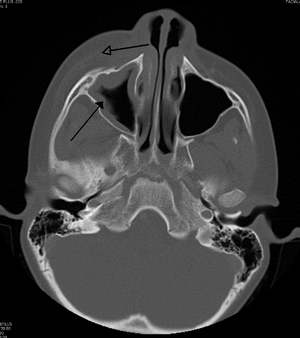

Periorbital cellulitis

Infection/inflammation of skin on and/or around the eyelid

image الإنجليزية

RtmaxobitinfectteethCT.png

١٬٠٦٨ × ١٬٢٠٥؛ ٨٠٩ كيلوبايت